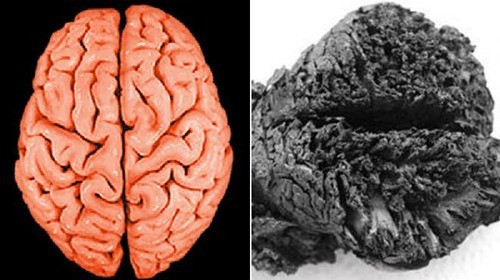

Trong cuộc khai quật tại Seyitomer Hoyuk, Thổ Nhĩ Kỳ, các nhà khảo cổ đã tìm thấy một bộ não người có niên đại hơn 4.000 tuổi được bảo quản tốt. Đây là một trong những bộ não cổ nhất từng được phát hiện và cũng là một trong những bộ não nguyên vẹn nhất. Ảnh: UC San Diego Health. Việc nghiên cứu bộ não nguyên vẹn theo thời gian giúp các chuyên gia giải mã được nhiều thông tin về tình trạng sức khỏe, thời gian và nguyên nhân tử vong... Ảnh: Haliç University Istanbul.

Theo nghiên cứu của các chuyên gia tại Đại học Zurich ở Thụy Sĩ, bộ não trên thuộc về một người từng bị vùi lấp trong khu vực từng xảy ra động đất. Trận động đất này đã vùi lấp nhiều người trước khi hỏa hoạn bao trùm các khu vực đổ nát. Ảnh: Altinoz et al. via New Scientist. Ngọn lửa đã hút hết khí oxi và làm bốc hơi nước có trong bộ não. Việc hút cạn khí oxi và độ ẩm đã giúp bộ não được bảo tồn nguyên vẹn suốt hàng ngàn năm. Ảnh: LiveScience.

Thêm nữa, bộ não được bảo quản nguyên vẹn nhờ nằm trong lớp đất có lượng kali, magie và nhôm khá cao. Ảnh: huffpost. Khi các loại chất hóa học trên phản ứng với axit béo trong mô của con người chúng sẽ tạo thành chất adipocere, một loại sáp vật chất giúp bảo quản bộ phận cơ thể người. Ảnh: huffpost.

"Mức độ bảo quản kết hợp với niên đại của bộ não thật đáng kinh ngạc", nghiên cứu của các chuyên gia chỉ ra. Ảnh: huffpost. Mời độc giả xem video: Hé lộ nền văn minh đã mất tích qua tàn tích khảo cổ.